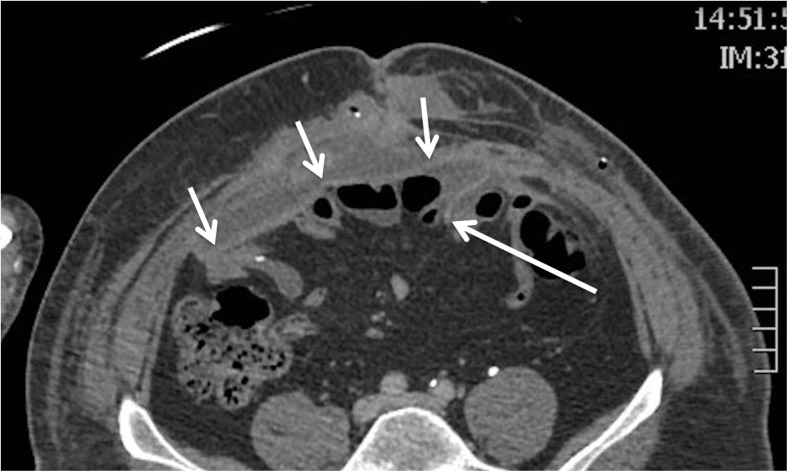

Not only does mesh position affect the radiological appearances but it also influences the development of mesh-related complications and mechanism of any hernia recurrence [18]. For example, intra-abdominal or inlay meshes may become detached laterally, especially if tacked inadequately (Fig. 3). Detachment does not happen with onlay or sublay repairs because mesh is encapsulated within a plane rather than being tacked to its margin. Abdominal viscera are in direct contact with intraperitoneal mesh, which encourages small bowel perforation, fistula and adhesions. To counter this, some meshes are coated posteriorly but uncoated anteriorly, to encourage ingrowth. Alternatively, omentum is interposed between mesh and viscera. Conversely, onlay mesh is more associated with superficial wound infection [19].

Fig. 3.

Postoperative axial CT showing an intraperitoneal mesh (short white arrows). The mesh has become detached (white long arrow), with the left lateral edge coming to lie several centimetres deep to the anterior abdominal wall. This offers the opportunity for recurrence at this site and may also cause deep adhesions